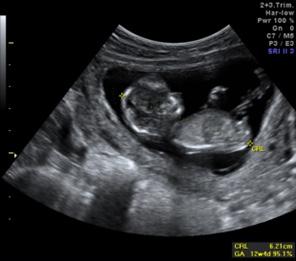

En la del I trimestre (10-14 semanas), se confirman la gestación, la edad gestacional de forma más precisa midiendo la longitud craneocaudal (LCC)

(ENAM EXTRA 2021), y la vitalidad del embrión (actividad cardiaca) (ENAM EXTRA 2020)

Figura 35. Pruebas invasivas Figura 36. Ecografía de I trimestre medición de la ICC

Número de fetos, viabilidad fetal Edad gestacional Translucencia nucal